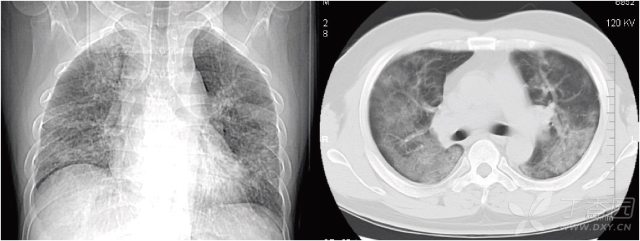

胸部ct 入门 这6 种征象最常见 丁香园